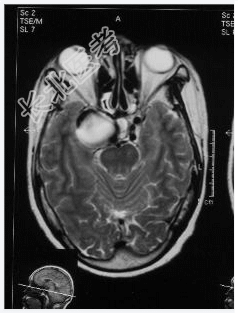

- [材料题] 患者,女性,59岁,因复视、右面瘫及蚁行感半年,间有头疼,无呕吐入院。体检:神清,右外展不全,复视,右面部皮肤感觉尚好,伸舌居中,右指鼻试验(-),四肢(-)。做头颅MRI检查。

- 简答题1、请问诊断是什么?

- 简答题2、诊断依据是什么?

- 简答题3、鉴别诊断有哪些?